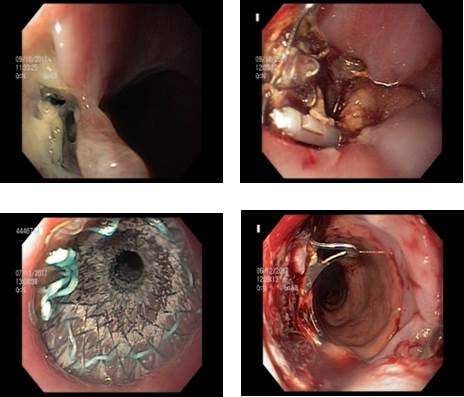

Luego de la cirugía no reitera fiebre, presenta buen estado general, pero se constata persistencia de gasto por drenaje constituyendo una fístula gástrica. Se realiza video gastroscopia (VGC) donde se visualiza orificio fistuloso inmediatamente por debajo de la unión gastro esofágica, sobre la línea de sutura. Se coloca clip Ovesco® (12mm, tipo gc, marca Ovesco, Tübingen, Alemaña) a nivel del orificio fistuloso con posterior colocación de 2 clips y sonda nasoyeyunal de alimentación con el objetivo de asegurar el cierre de la misma y asegurar una correcta nutrición respectivamente. Se realiza estudio contrastado de esófago gastro duodeno de control a las 3 semanas, observando la persistencia de fuga de contraste a nivel del orificio fistuloso. Se decide la colocación de stent metálico autoexpandible parcialmente recubierto ((23/18 mm de diámetro, Boston Scientific Corporation, Natick, MA, USA) para ocluir el orificio fistuloso. Presenta buena evolución a las 48 horas, con disminución franca del gasto por el drenaje, que posteriormente se agota (fig.1). Se realizó la extracción del stent a las 8 semanas tras su colocación, sin incidentes. La cicatrización de la fuga se confirmó mediante endoscopia e inyección de contraste.

La endoscopía es de suma utilidad para diagnosticar y topografiar la fístula, permite descartar alteraciones anatómicas que puedan actuar como elementos favorecedores de su persistencia (como la estenosis de la manga o un “twist” de la misma que actúa a modo de estenosis funcional), y mediante diversas técnicas, contribuir a acelerar el cierre de esta 7. Se han descrito procedimientos muy diversos y con resultados dispares, como colocación de clips de tipo Ovesco® o stents recubiertos, drenajes internos de colecciones, dilatación de una eventual estenosis con balón de acalasia e inyección de cianacrilato sobre el orificio fistuloso. En el caso que presentamos se utilizó en primera instancia un clip Ovesco® con posterior colocación de un stent metálico auto expandible parcialmente recubierto a las 3 semanas dada la persistencia de fuga de contraste a nivel del orificio fistuloso. Tanto la utilización de clips Ovesco® como de stents tienen mayor tasa de éxito si se colocan dentro de las tres semanas de la aparición de la fístula, disminuyendo su efectividad en el caso de las fístulas crónicas. De diagnosticarse una estenosis mesogástrica, esta actúa como un factor hipertensivo sobre la manga, por lo que debe dilatarse (para lo que puede requerir tres o más sesiones). Las colecciones o cavidades intermedias deben drenarse (interna o externamente), ya que contribuyen a perpetuar la fístula. El estudio de Shehab y colaboradores sobre pacientes con fístula post cirugía bariátrica describe tasas de éxito de hasta el 82% combinando el uso de clips Ovesco® y stents, con una media de 3 procedimientos por paciente 8. La tasa de complicaciones en el uso de stents es cercana al 30%, fundamentalmente migración, sangrado e intolerancia al mismo lo que obliga su retirada.